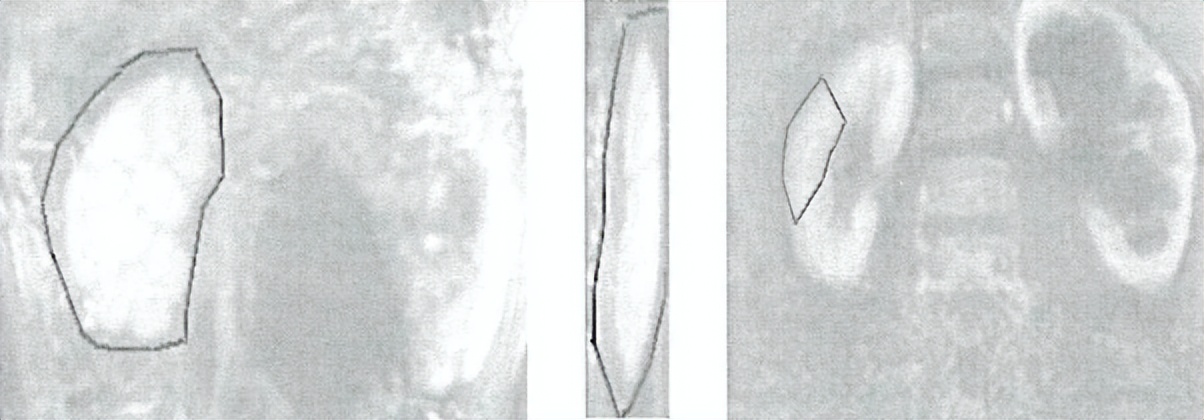

(4)ROi的绘制

A b

C d e

a:ROi放置于主动脉周围最大强化处

B:之后在肾动脉水平或正上方放置一块较小的ROi

c:选择肾盂里刚开始出现造影剂的那一期图像,并选取前面一期勾画整体的肾脏

D:在侧向视图中勾画出全肾

e:肾实质的勾画,对肾实质过多或者或少的勾画都会影响实验结果,勾画完成后,肾实质增强曲线,肾盏排泄曲线,SRf情况软件自动生成。